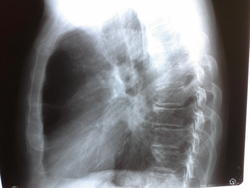

в проекции н/долевого бронха тень доп. Образования, сгущение лег. Рисунка нижней доли. Cr?..лаборант зачем-то снял левый бок...ему видимо все равно, какой было снимать.( карте терапевт назначил в 2-х проекциях)

А в переднем средостении парастернально-это буллы?

А снимок, если он цифровой, может быть и правый. На цифре боковые наоборот выглядят.

Наверное, буллы. Написал бы, что данные изменения более характерны для сердечных дел.

По-моему доп. образование в проекции корня, ближе к центральному раку, +гипо средней доли. И лево-право при боковом не сильно влияет. Сначала бы просто пневмонию написать, с контролем для искл. объемного образования. Неделя для онко - не экстренно, (а м.б. боже поможе - и пневмония)